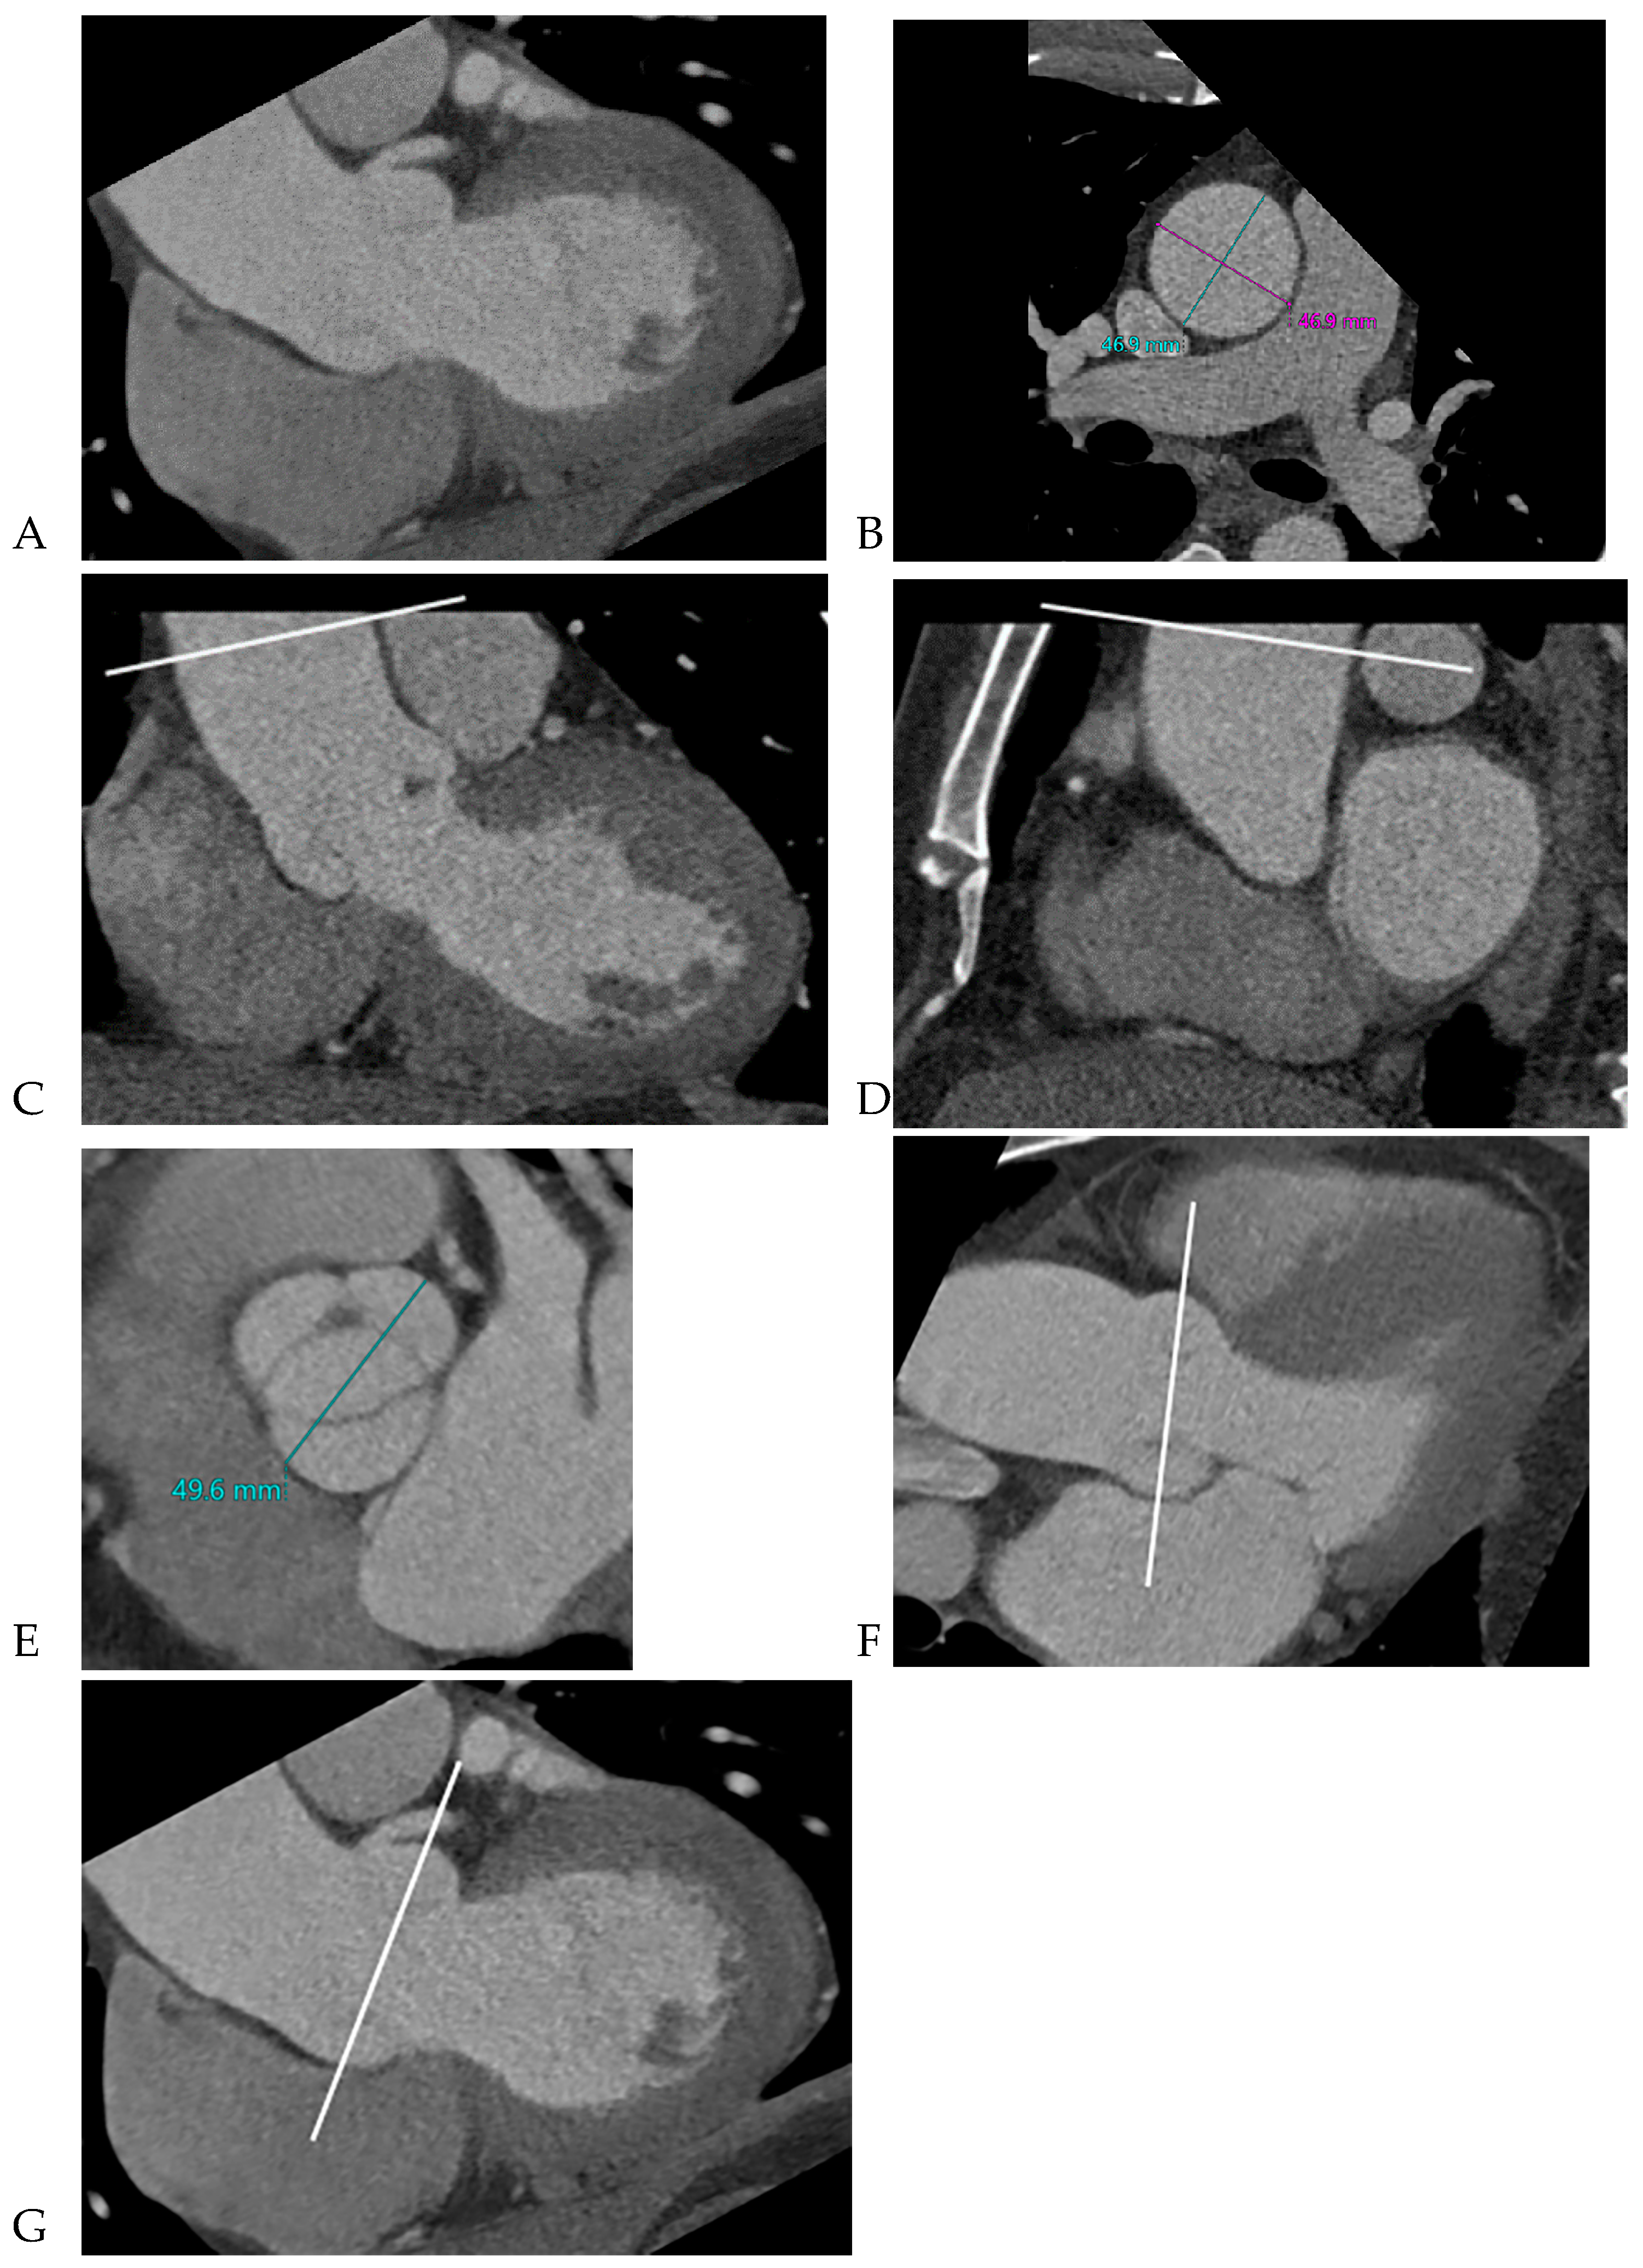

All CCT images were reviewed by a consensus of two radiologists with 16 and 5 years of experience, respectively, who were blinded to the clinical and surgical data. BAV was defined as the presence of two cusps and commissures in both systole and diastole. The following morphological variables were assessed: (1) presence or absence of raphe and (2) ascending aortic diameter. The term “raphe” defines the conjoined or “fused” area of two adjacent undeveloped leaflets that turn into a malformed commissure between both leaflets [9]. BAV morphology was classified as raphe+ or raphe- according to the presence or absence of raphe (Figure 1) [10]. The dimensions of the ascending aorta were measured at the sinus of Valsalva and tubular portion. Double-oblique coronal images of the ascending aorta were reconstructed at 10 % or 20 % of the cardiac cycle (early to mid-systole) to measure the tubular portion of the ascending aorta dimensions. The measurement of the maximum dimension of the aortic sinuses of Valsalva was performed using a double oblique transverse view of the aortic root at 10 % or 20 % of the cardiac cycle (Figure 2). Aortopathy refers to progressive dilatation of the ascending aorta and is defined as indexed maximal aortic diameter exceeding 21 mm/m2 of the body surface area (BSA) [11]. Ascending aortic dilation configurations were slightly modified from the Fazel classification, which was assigned to four types depending on whether the segment of the vessel was exclusively or predominantly involved in dilatation: normal aorta, type 1, isolated dilation of the ascending aorta root at the level of the sinus of Valsalva [12]; type 2, middle ascending dilatation at the level of the tubular ascending portion; and type 3, combined dilatation of the aortic root and mid-ascending aorta (Figure 3) [12]. Aortic aneurysms are defined as those with dimensions greater than 50 mm. The association between the presence of raphe and the risk of aortic valve dysfunction and aortopathy was also analyzed.

Figure 1. Bicuspid aortic valve classification: Valve type according to absence (A and B) or presence (C and D) of raphe.